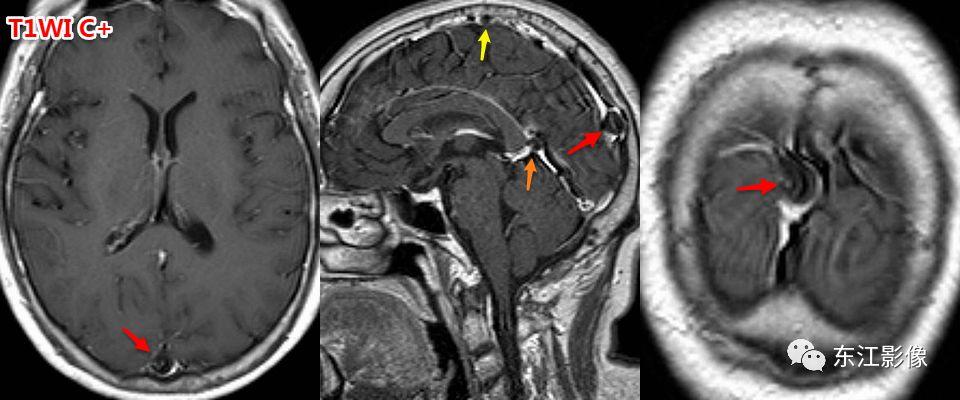

5. 脑脊液流动伪影

- 脑脊液流动伪影主要见于T2WI、FLAIR,主要是长TE序列容易出现流空效应的缘故。

- 但由于脑脊液流动方向、速率不一等因素的影响,呈现为非脑脊液信号影像,部分呈囊样。

- 常见于第三脑室、侧脑室室间孔旁区、脑干周围脑池(这些区域结构复杂)。

- 鉴别要点,T1WI、增强未能辨认;DWI与邻近一致的无信号;无占位效应。

又一例。